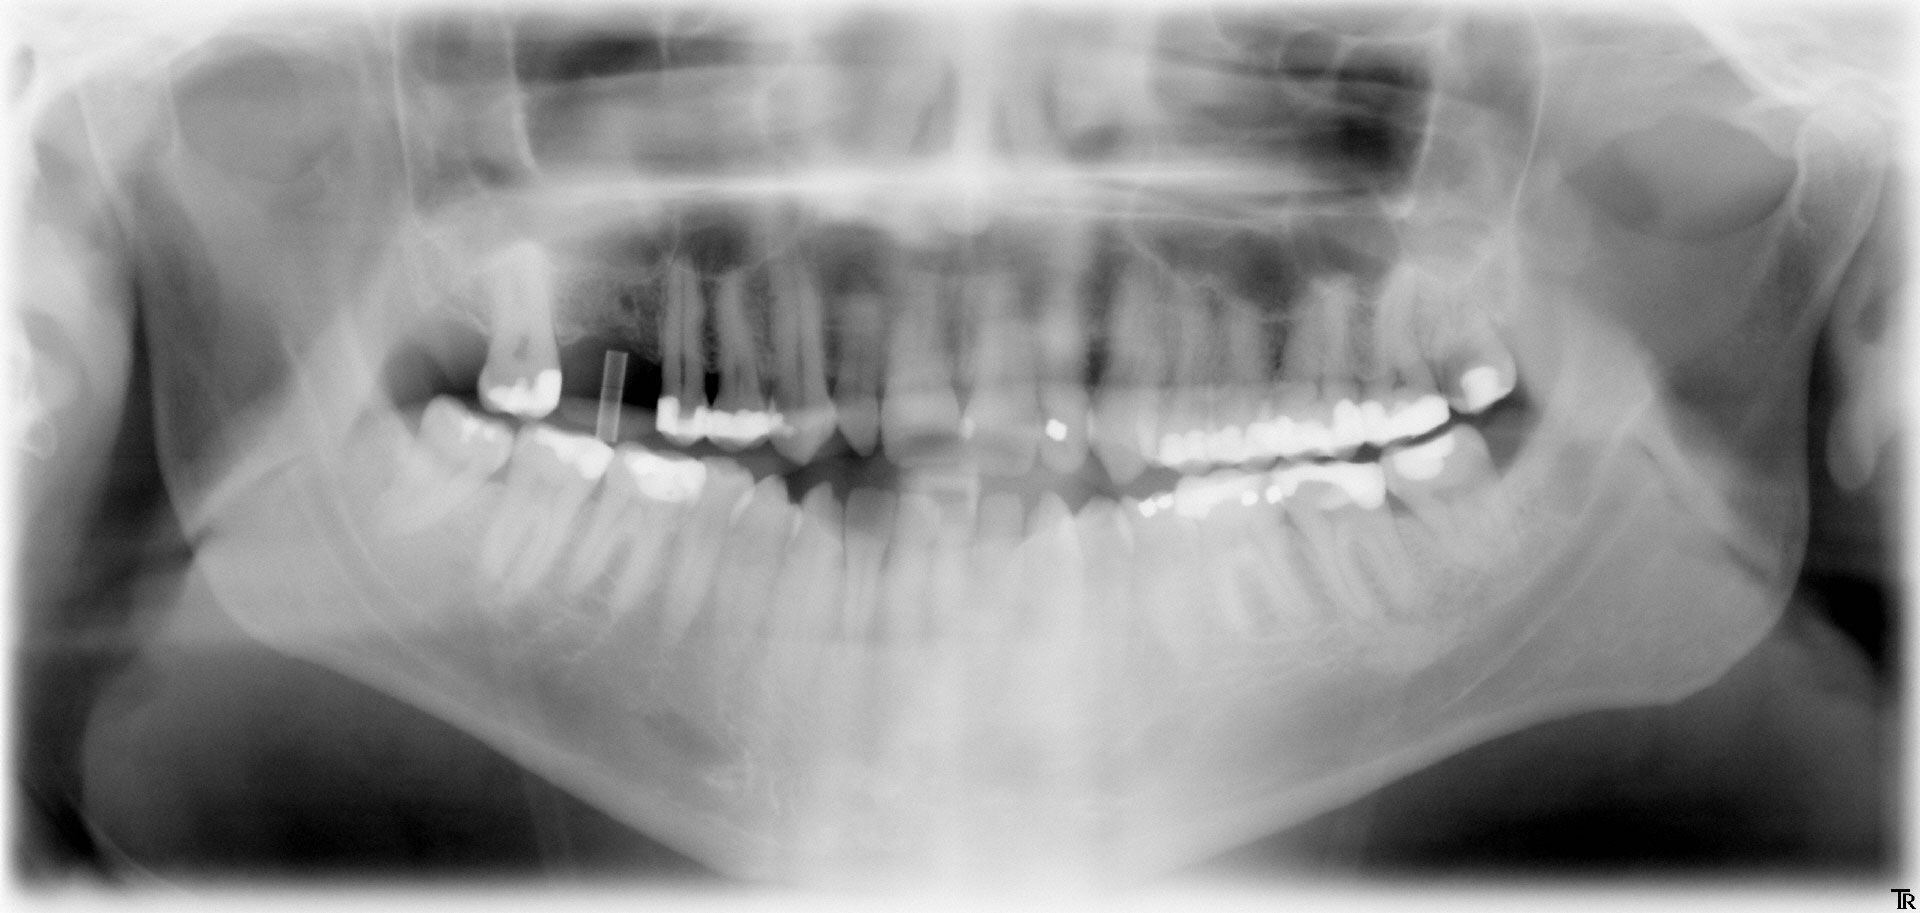

Panorama-Röntgenaufnahme

Implantat im Oberkiefer

Für ein Implantat werden sowohl eine Mindest-Knochentiefe als auch ein Sicherheitsabstand im Unterkiefer zum Nervenkanal vorausgesetzt. Die Knochentiefe wird durch spezielle Röntgendiagnostik ermittelt.

Die reale Knochenhöhe wird mit Hilfe einer Tiefziehschiene mit eingearbeiteten Metallkugeln ermittelt. Bei digitalen Röntgengeräten kann gegebenenfalls auf die Messaufnahmen verzichtet werden, da sie über ein integriertes Messtool verfügen. Zur Detailabklärung kann es erforderlich sein, zusätzliche Aufnahmen von einzelnen Zahnabschnitten zu machen.

Durch die Computertomographie kann die Lage der später zu setzenden Implantate im Vorfeld schon auf den Millimeter bestimmt werden.